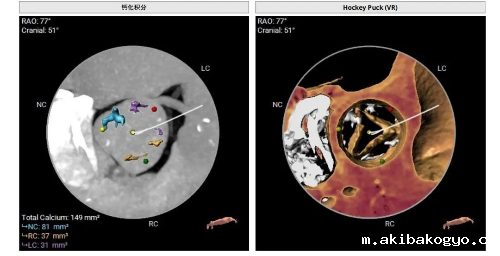

曾阿姨术前评估:轻度钙化,钙化积分共:149